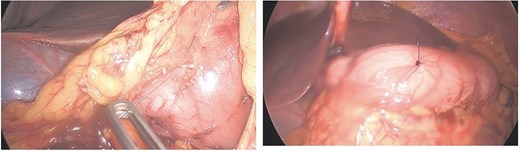

Given persistent pain and fever, a second-look laparoscopy was undertaken. Access to the lesser sac via the gastrocolic ligament revealed the metallic wire (Fig. 2), embedded near the pyloric region. It was successfully extracted without mucosal rupture or abscess formation.